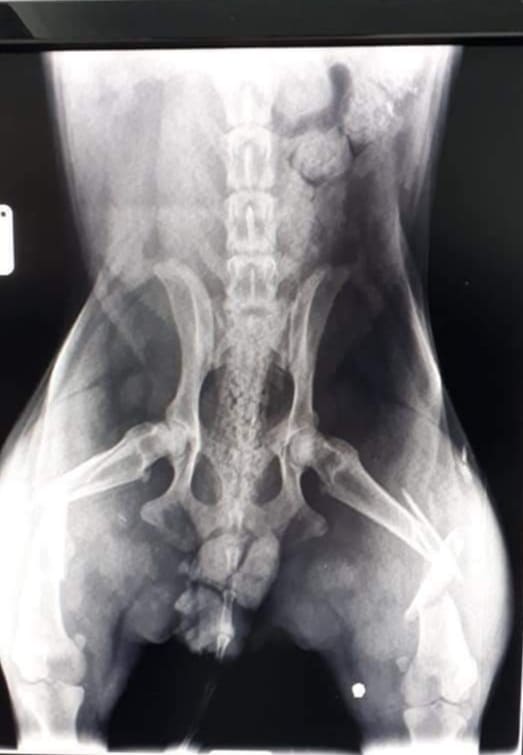

Stigli su i RTG snimci  na osnovu kojih su dijagnosticirane frakture obje butne kosti kao i fraktura tibie.

Na svu sreću kičma, zdjelica i vitalni organi su bez većih oštećenja.